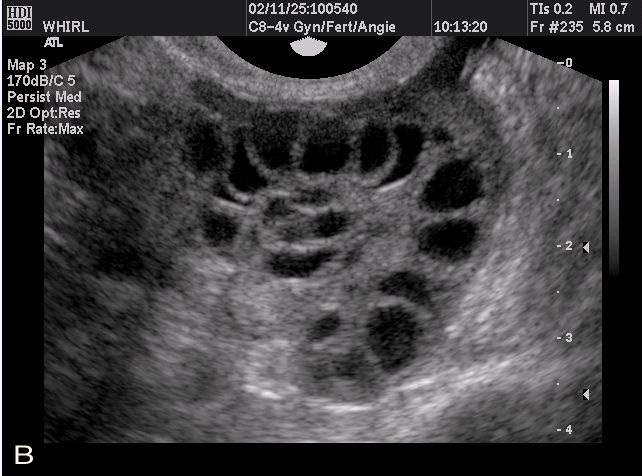

String of pearls

numerous follicles in ovarys een on ultrasound

*polycystic ovarian syndrome*